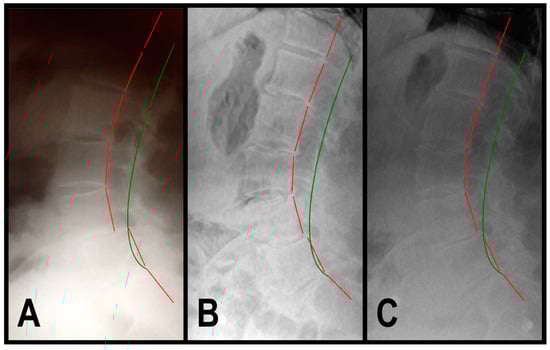

3.1.2. Patient 2

| ARA L1-L5 (°) | −40 | −49.9 | −42.2 | −43.6 | |

| Tz L5-S1 (mm) | 0 | 13.8 | 4.2 | 4.3 | |